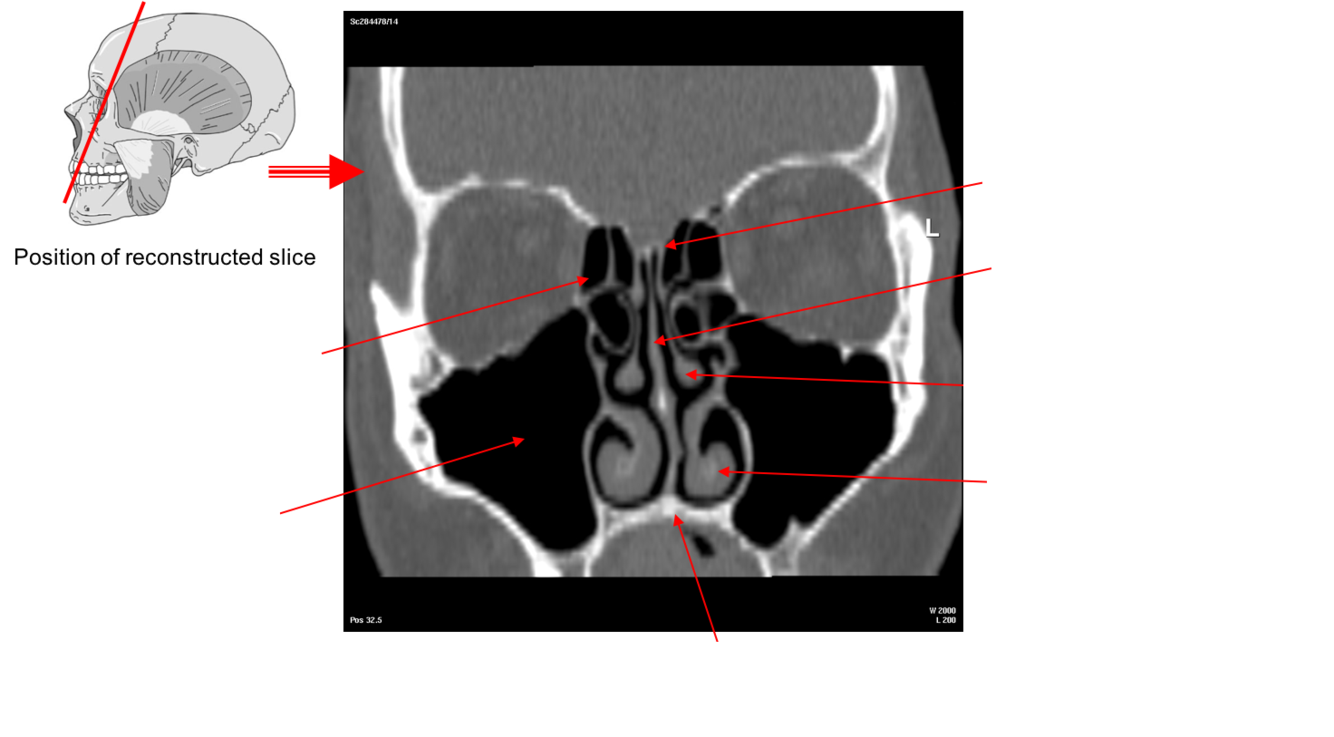

Label this image

The Nasal Conchae also called turbinates

These are thin scroll shaped bony plates that project into the nasal cavity. There are usually three the superior, middle and inferior nasal conchae (supreme may also be present).

•These conchae form passageways – the superior, middle and inferior meatae which are lined by mucous membrane

•This arrangement increases the surface area of the nasal cavities providing for rapid warming and humidification of air as it passes to the lungs.